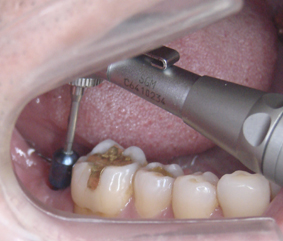

DSC01672.JPG

インプラントが歯肉の中に見えます

今回は麻酔の注射はしていません

写真の見える歯肉のくぼみに綿球で

表面麻酔を塗りました

骨ができ過ぎていたりすると

麻酔の注射が必要になることもありますが

痛いというほどのことはありません